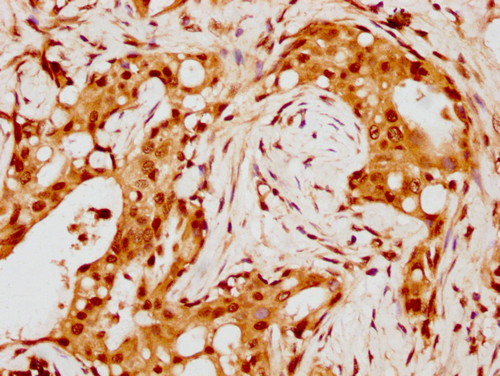

IHC image of CSB-PA010429PA88nohHU diluted at 1:8 and staining in paraffin-embedded human breast cancer performed on a Leica BondTM system. After dewaxing and hydration, antigen retrieval was mediated by high pressure in a citrate buffer (pH 6.0). Section was blocked with 10% normal goat serum 30min at RT. Then primary antibody (1% BSA) was incubated at 4°C overnight. The primary is detected by a biotinylated secondary antibody and visualized using an HRP conjugated SP system.